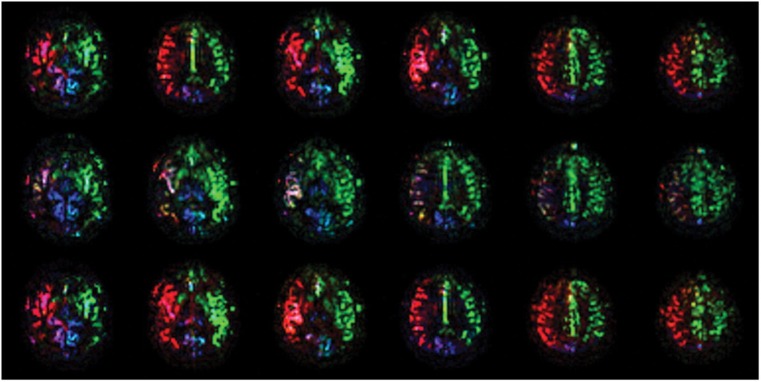

Material and methods: Two healthy volunteers were recruited. Anatomic features and flow directions in the circle of Willis were evaluated with time-of-flight magnetic resonance angiography (MRA) and two-dimensional phase-contrast (2DPC) MRA, respectively. Regional cerebral blood flow was visualized with territorial arterial spin-labeling magnetic resonance imaging (TASL-MRI). TASL-MRI and 2DPC-MRA were performed in three states: at rest, during manual compression of the right carotid artery, and after decompression. In one volunteer, time-space labeling inversion pulse (Time-SLIP) MRA was performed to confirm collateral flow.

Results: During manual carotid compression, in one volunteer, the right thalamus changed to be fed only by the vertebrobasilar system, and the right basal ganglia changed to be fed by the left internal carotid artery. In the other volunteer, the right basal ganglia changed to be fed by the vertebrobasilar system. 2DPC-MRA showed that the flow direction changed in the right A1 segment of the anterior cerebral artery and the right posterior communicating artery. Perfusion patterns and flow directions recovered after decompression. Time-SLIP MRA showed pial vessels and dural collateral circulation when the right carotid artery was manually compressed.

Conclusion: Use of TASL-MRI and 2DPC-MRA was successful for non-invasive visualization of the dynamic changes in regional cerebral blood flow during and after manual carotid compression.